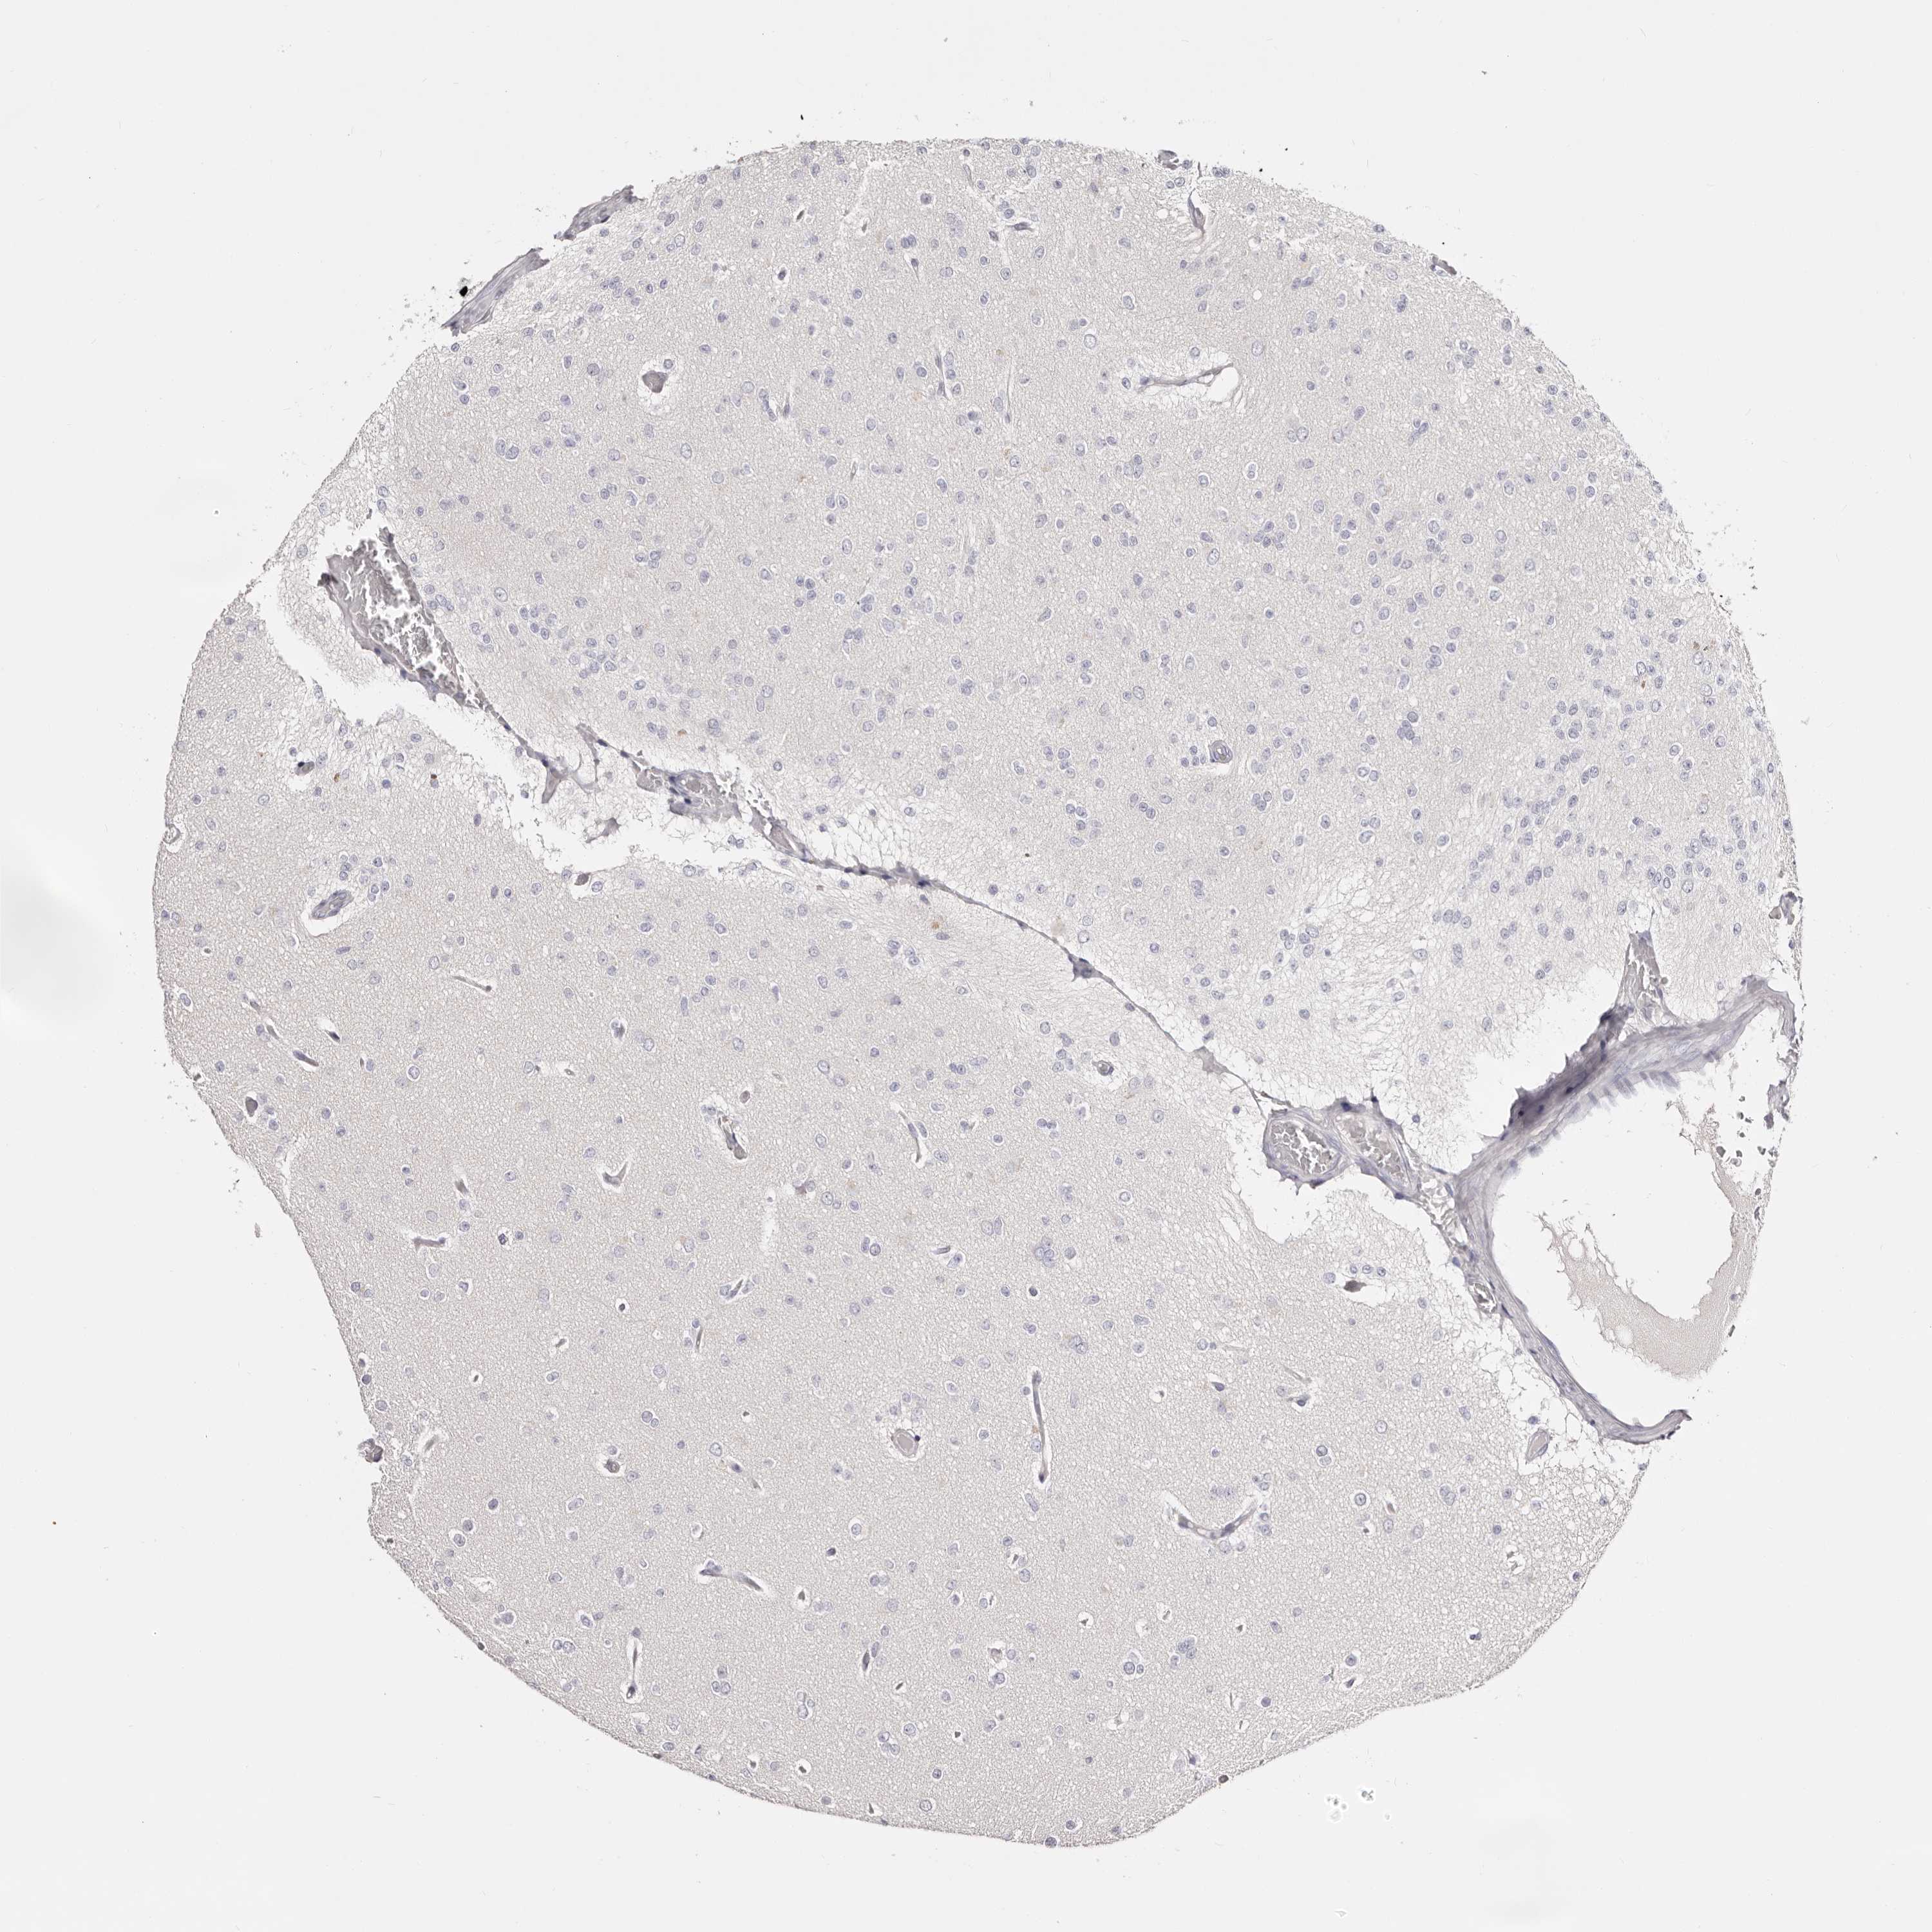

GLIOMA - Protein expressioni

A mouse-over function shows sample information and annotation data. Click on an image to view it in a full screen mode. Samples can be filtered based on level of antibody staining by selecting one or several of the following categories: high, medium, low and not detected. The assay and annotation is described here.

Note that samples used for immunohistochemistry by the Human Protein Atlas do not correspond to samples in the TCGA dataset.

Antibody stainingi

Antibody staining in the annotated cell types in the current human tissue is reported as not detected, low, medium, or high, based on conventional immunohistochemistry profiling in selected tissues. This score is based on the combination of the staining intensity and fraction of stained cells.

Each image is clickable and will lead to virtual microscopy that enables deeper exploration of all samples and also displays staining intensity scores, fraction scores and subcellular localization as well as patient and tissue information for each sample.

Antibody HPA030270

Antibody HPA030271

Antibody HPA030272

Staining

High

Medium

Low

Not detected

Intensity

Strong

Moderate

Weak

Negative

Quantity

>75%

75%-25%

<25%

None

Location

Nuclear

Cytoplasmic/membranous

Cytoplasmic/membranous,nuclear

Glioma, malignant, High grade

Glioma, malignant, Low grade

Glioblastoma, NOS